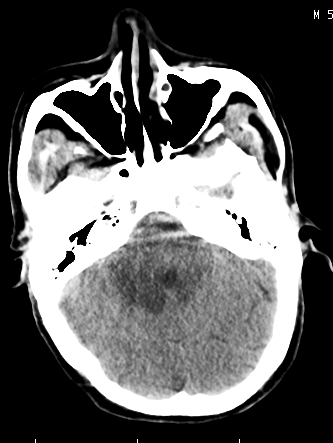

m/50,头昏头痛1月,近3天感觉左半肢体活动不利,自述半年前呈患肺tb,腰穿脑脊液未见特殊改变。现做头颅ct请大家会诊。

ct值?是囊变?梗塞软化灶形成

考虑颅内感染性病变:结核可能性大。

结核性脑膜炎,结核瘤,梗塞灶三症并存,提示颅内结核感染可能性大。

感染性病变;脑干脓肿(脓肿壁形成期),基底节及内囊(脑炎期)。顺便问一句,该病人是不是抵抗力很差,有没有糖尿病。

右侧基底节区缺血性脑梗塞.脑干区考虑结核.

可考虑结核,患者水肿范围大,囊性病灶边缘密度较高,不考虑胶质母细胞瘤